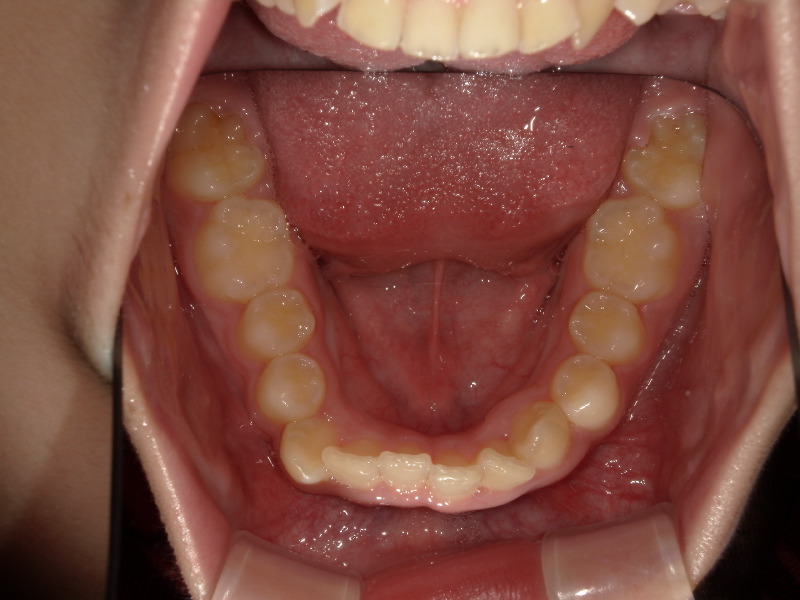

半年後の下の歯の写真です。

がたつきがあったのも綺麗になり、調和の取れた歯並びへ変わってきています!

舌のアクティビティーが少し苦手だったり受験などもあり、3年ほどかかりましたがアクティビティー卒業する頃には綺麗な歯並びになりました!

下の歯もしっかりと見えています。